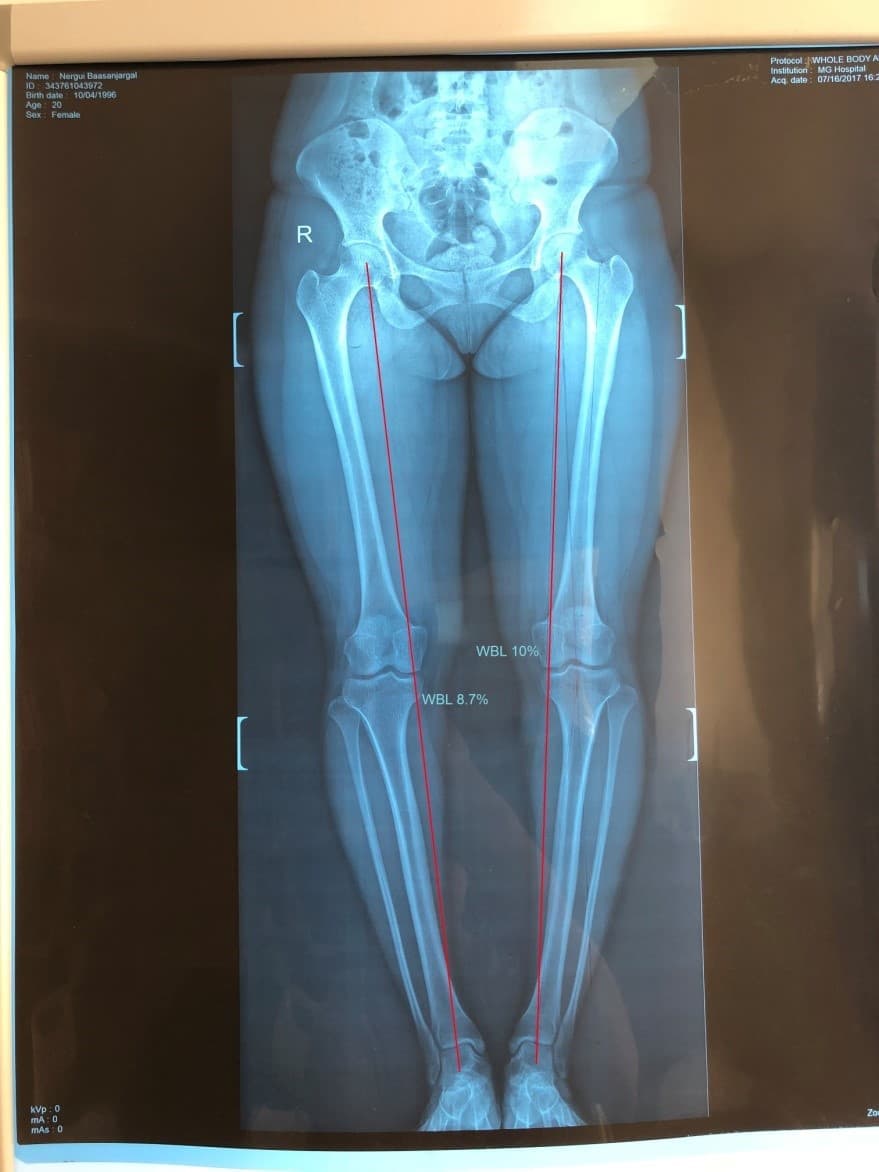

Биеийн жингийн шугамыг мэс заслын өмнө болон мэс заслын дараа хэмжсэн байдал

Шаантны дотор дээд өнцөг мэс заслын өмнө баруун хөлд 84o, зүүн хөлд 82o байсан бол мэс заслын дар аа баруун хөлд 96o, зүүн хөлд 94o болж засагдсан байдал.